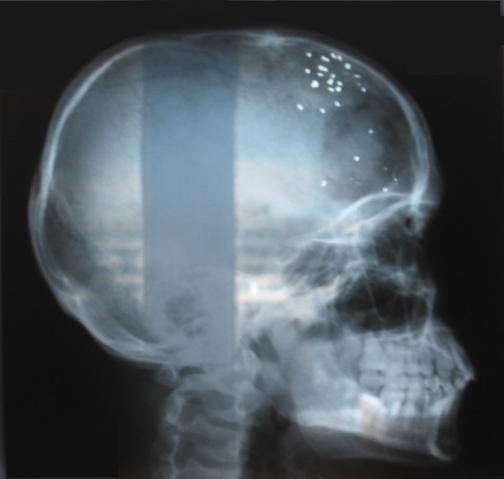

Промышленные рентгены имеют высокую энергию, но не слишком большую дозу. Да, стационарный аппарат может неслабо засветить, но чаще всего за несколько секунд доза будет не критической.